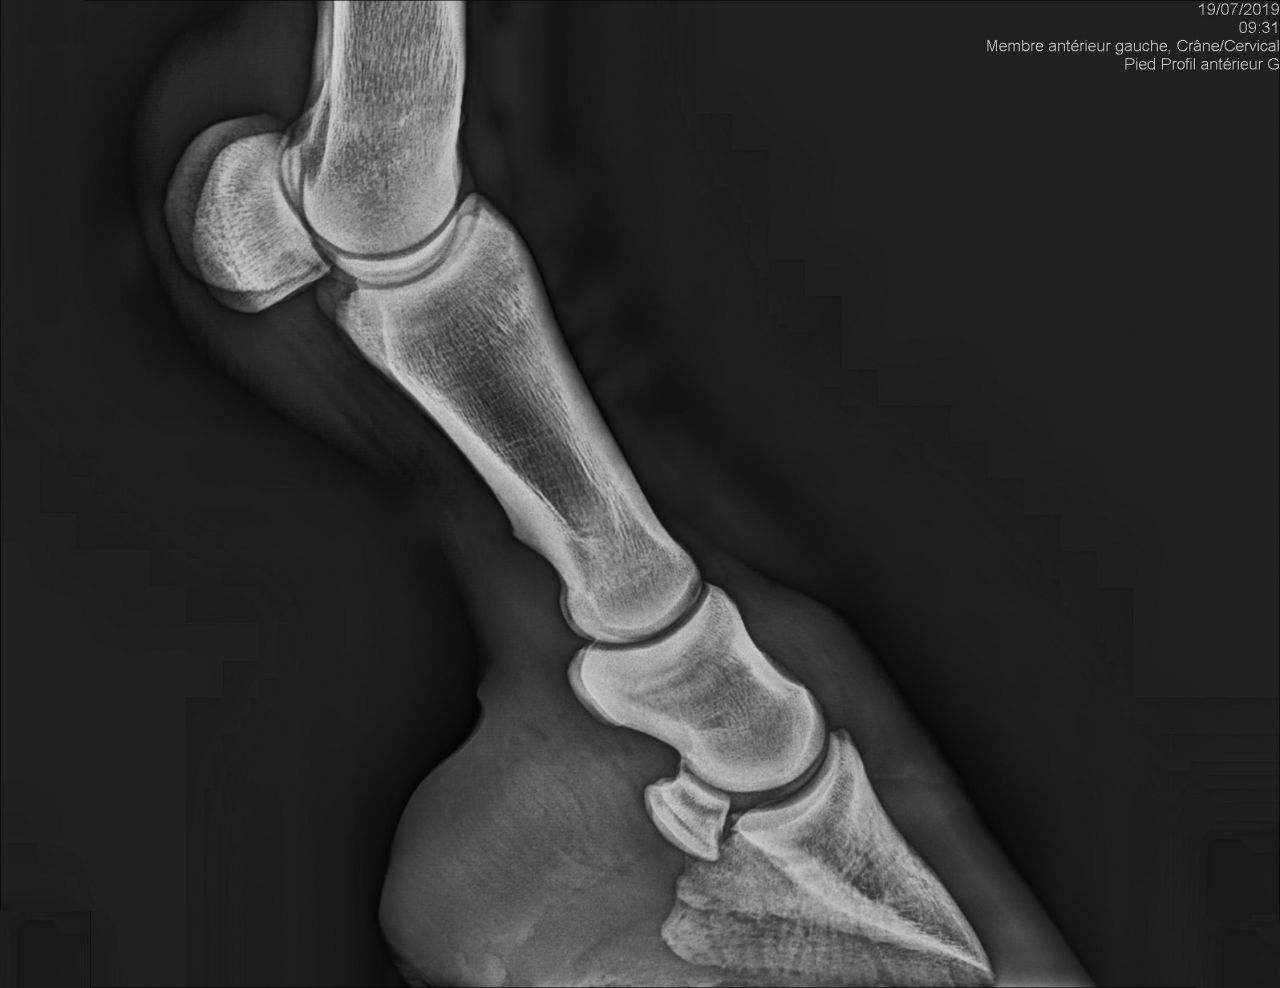

| Dire merci | Bonjour J'ai fait un bilan radio à ma mule qui est irreguliere pour recherche de la cause de sa sensibilité. Le veto m'envoie ce cliché de profil. C'est moi où on ne peut juger de l'épaisseur de la sole et que c'est le premier truc à regarder dans pareil cas ? Merci par avance pour vos avis éclairés... j'en ai d'autres de face et derrière si certains seraient capable d'évaluer la sole... Quand je demande au veto qui me parle absolument pas de pb de sole il me répond évasif "Ah oui peut être un peu fine" ![]() ![]() Édit: ajout photo de dos Message édité le 29/07/19 à 19:52 [edit modo suppression coordonnées véto] Ce message a été modifié par un modérateur. |

| Dire merci | Un petit up . J'ai tort d'être fâchée? J'aimerais savoir si ma remarque est pertinente ou pas en fait. J'ai tjs vu des radios de profils qui ne coupaient pas la sole... |

| Dire merci | Si : ras sauf légère demineralisation de P3 . Tester réaction aux AI Donc bon moi je veux bien hein mais la première chose à savoir et surtout si la seule anomalie est sur la phalange c'est est ce qu'elle est protégée convenablement... Non? J'espère avoir tort c'est pas mon métier mais je n'ai malheureusement pas assez confiance. Donc même si il se trompe sur le diag c'est pas tellement grave, mais je paye pas un photomaton qui me prend la moitié du visage. Donc c'est ma question ... cette radio est elle acceptable dans le cas d'une recherche d'explication pour pied sensible? |

| Dire merci | Franchement je lui demanderai de refaire le premier cliché qui n est pas du tout cadré on ne voit même pas le bas. Ou alors c est moi c est que sur mon téléphone ça ne s ouvre pas correctement |

| Dire merci | Même avis : on devrait voir un bout de la planche ! Comme sur l'autre cliché. Mon véto a limage en direct sur son ordi, ça arrive souvent que le 1er cadrage ne soit pas terrible : il recommence immédiatement sans me compter l'essai foireux. |

| Dire merci | Pareil, premier cliché inexploitable pour voir la sole correctement... |

| Dire merci | Disons que ça dépend ce qu'il voulait voir, s'il voulait les articulations c'est bon, s'il voulait une photo du pied c'est coupé c'est clair ! Mais je pense qu'il cherchait une photo des articulation, sur une photo de pied l'articulation du boulet est souvent coupée (cf radio de cody) Elle est bizarre d'ailleurs ta radio goss, on voit pas du tout la boîte cornée |

| Dire merci | zapi merci je pense que tu as raison! Il voulait prendre le boulet avec. En tt cas ça me paraît le plus probable et recevable argument. Je reste déçue de ne pas avoir un cliché de la sole mais pas de scandale à faire. |